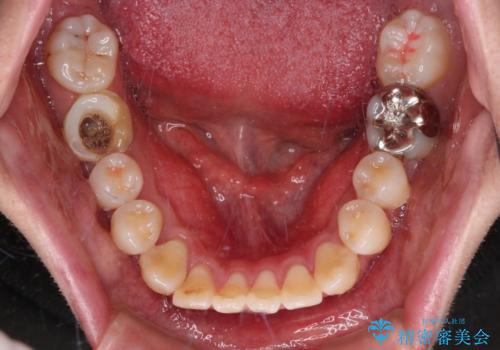

- 「横から見ると唇が前に出て見えるのが気になる…」

「マスクを外すのが恥ずかしい…」

そんな口元の突出感に悩まれてご来院された患者様。

精密検査の結果、上下左右の小臼歯4本を抜歯し、そのスペースに前歯を後方へ移動させる矯正治療をご提案しました。